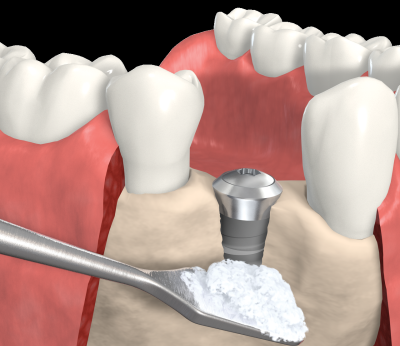

Χειρουργική Τοποθέτηση Μονήρους Εμφυτεύματος με Προστομιακό Έλλειμμα και Οστική Ανάπλαση

Κατά τη χειρουργική τοποθέτηση οστεοενσωματούμενου εμφυτευμάτος με σωστή φορά ένθεσης, προσθετικά καθοδηγούμενη, υπάρχει πιθανότητα κάποιες σπείρες του εμφυτεύματος να μην καλύπτονται από το φατνιακό οστούν.